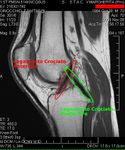

معرض الصور